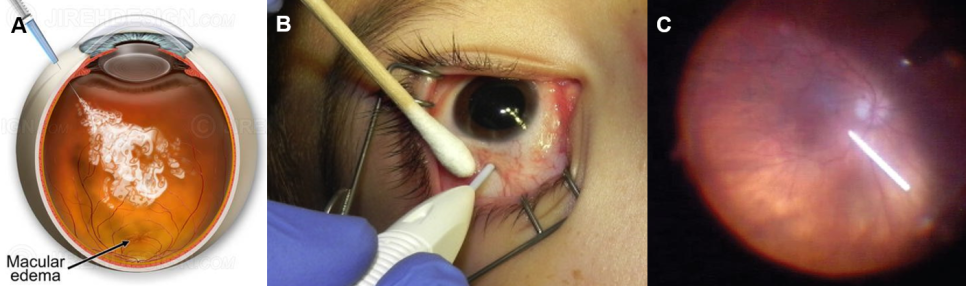

- 부신피질호르몬제(스테로이드, Corticosteroid): ‘단기간 효과’는 분명하지만 ‘장기간’ 사용 시 부작용에 항상 주의해야 합니다.① 작용 원리γ 인지질분해효소(Phospholipase) A2를 억제하고 염증성 매개 물질인 ‘프로스타글란딘(Prostaglandin; PG)’ 생성을 감소시킵니다.㉡ 대식세포와 중성 백혈구의 이동을 억제하고 모세혈관 투과성과 혈관 확장도 감소시킵니다.② 국소 점안 스테로이드(안약): 첫 번째 치료제로 고려합니다.③ 눈 주위 주사(그림 1): 안약 치료 후 재발하는 CME에 사용합니다. 유리체강내 주사보다 부작용이 적습니다.

그림 1. (A)테논난하트리암시놀론(Sub-Tenon Triamcinolone) 주입술, (B) 주사 전 CME, (C) 주사 2개월 후 호전-중심 오목 형태가 유지 중 ④ 유리체강 내 주사 ⑤ 트리암시놀론(Triamcinolone, 그림 2-A) : 혈액망막 장벽(Blood Retinal Barrier; BRB) 파괴를 감소시킵니다.* 재발성 CME에 유용하지만 효과가 일시적이기 때문에 일정 기간이 지나면 재발합니다. →효과를 유지하기 위해서는 여러 번 주사를 맞아야 합니다.㉡ 덱사메타손 삽입물(Dextamethasoneimplant; Ozurdex®, 그림2-B&C): 보다 효과가 오래 유지되지만 여전히 재발로부터 자유롭지 못합니다.